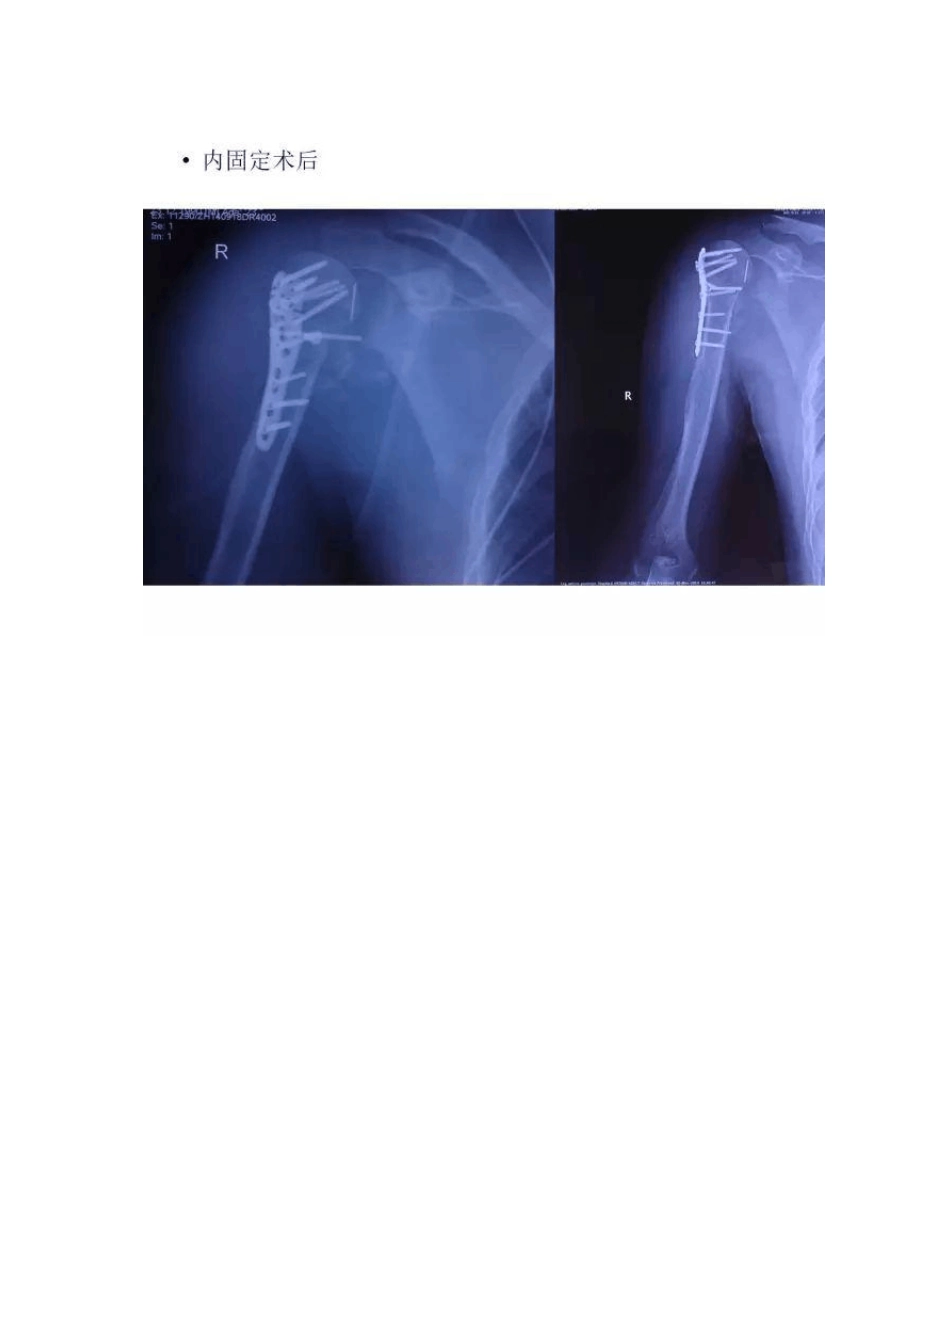

病例探讨病例摘要一:既往体健二:体格检查右肩前方可见长约15cm瘢痕局部皮肤无红肿、无压痛,皮肤温度不高右肩皮下可扪及肱骨断端右肩前屈上举40°,后伸 30°,外展 40°右上肢远端感觉血运活动正常三:肩关节评分Neer评分 15分ASES评分 3分Constant-Murley评分 28分肱骨近端骨折发生率:约占四肢骨折的4%~5%男:女=1:3[2]•多发生于老年人(>60岁,平均 72岁)约30%发生于年轻人平均年龄约30岁致伤机制:直接暴力(高能量损伤),如交通事故、体育竞技等治疗难点:内固定术后感染锁定钢板螺钉感染率 3.5%内固定术后 90天内清创引流 1.2%治疗目标:消除感染,挽救肩关节肱骨头缺如病因:肱骨头缺血坏死、吸收Gorham-Stout综合症(大块骨溶解症)肩关节结核色素沉着绒毛结节性滑膜炎肱骨近端各种良恶性肿瘤慢性化脓性骨髓炎肩关节融合术适应症:感染漂浮肩骨质良好的年轻重体力劳动者不可逆性上肢臂丛神经损伤肩关节假体置换/翻修失败严重的盂肱关节骨缺损肩部肿瘤/病损切除术后重建肱骨近端慢性骨髓炎化脓性/结核性盂肱关节炎难治性肩关节不稳定合并肩袖、三角肌功能障碍的肩关节假性瘫痪小结肱骨近端骨折内固定术后感染导致肱骨头缺如治疗是肩关节外科的难点主要治疗目的是消除感染和挽救肩关节肩关节融合术和反式肩关节置换术都是治疗肱骨头缺如的良好选择和有效补救综合多种因素谨慎选择治疗方法是治疗成功的关键反式肩关节置换术适应症:非重体力劳动严重骨质疏松症肩袖功能障碍无法复位的肱骨大结节骨折肱骨近端陈旧性骨折不愈合(或合并骨缺损)半肩关节置换失败翻修陈旧性锁定前脱位三角肌功能正常且肩胛盂骨质良好接受肩关节假体存在预期寿命的问题绝对禁忌症:腋神经损伤/三角肌功能不良相对禁忌症:年龄<65岁解剖与功能三角肌(替代肩袖功能):前束——收缩使肩关节前屈并略旋内中束——收缩时与冈上肌协同外展肩关节后束——收缩使肩关节后伸并略旋外反肩假体特点——更好的发挥三角肌功能:旋转中心内移——降低肩盂假体松动发生率假体颈干角155°(正常130°)——肱骨干假体下移增大三角肌张力——更多三角肌纤维参与运动对于进行反式肩关节置换手术的患者,术中重建大小结节组的功能优于...